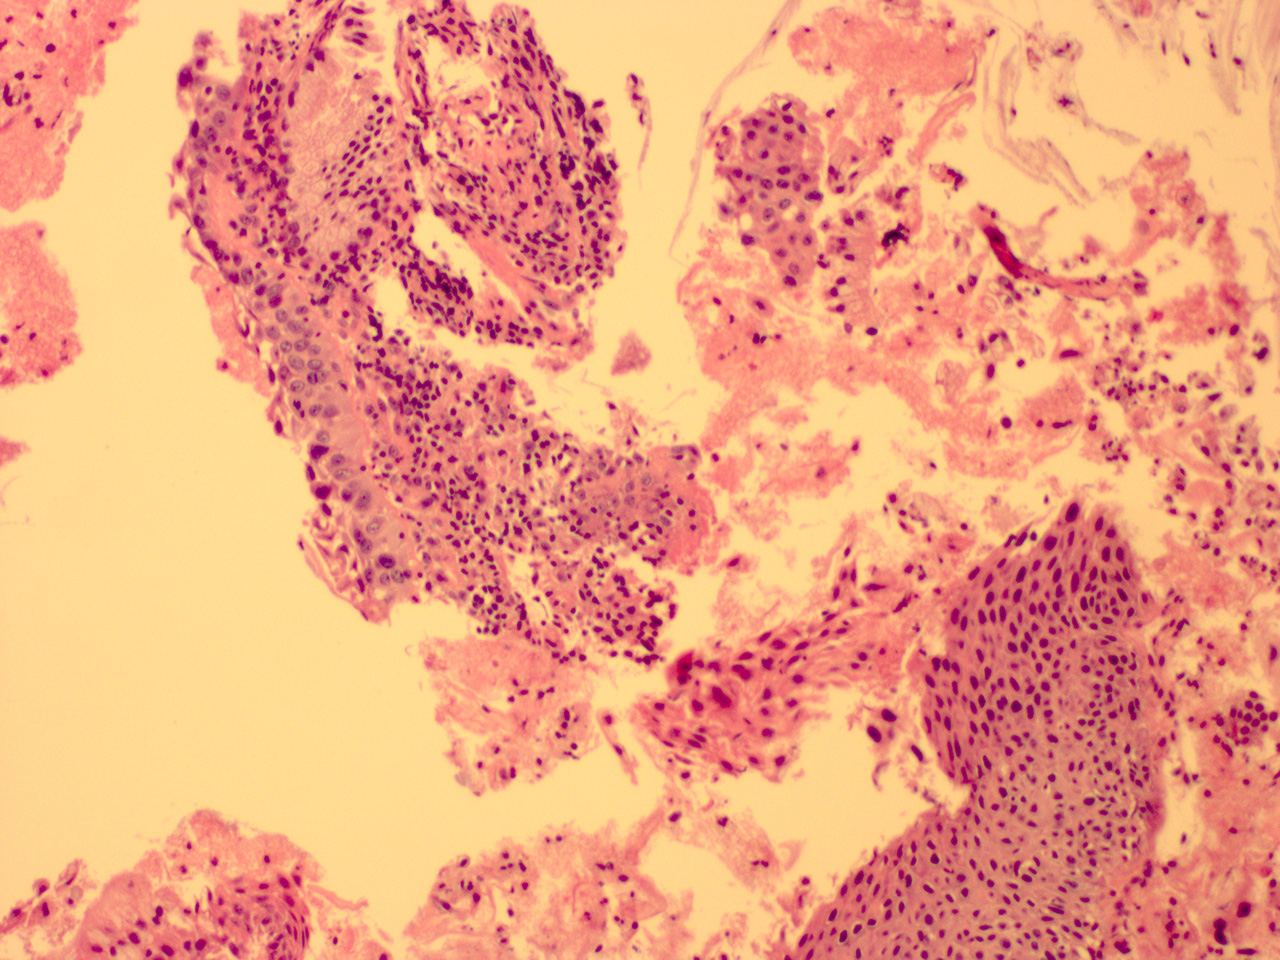

![]() Case 3

Soft Bx CIN 3

10x - Low Power |